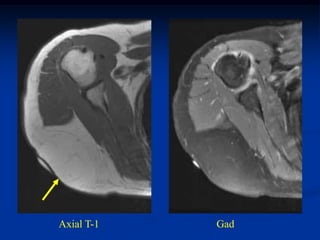

Case #297.2     Hemangioma forearm

46 yr male with

tender soft mass

forearm for years

Cor T-1   T-2   Gad

Sag T-1   T-2   Gad

Axial T-1         T-2

Gad

Case #297.2 Hemangioma forearm 46 yr male with tender soft mass forearm for years

• 310.

• 311.

• 312.

Axial T-1 T-2 Gad

• 313.